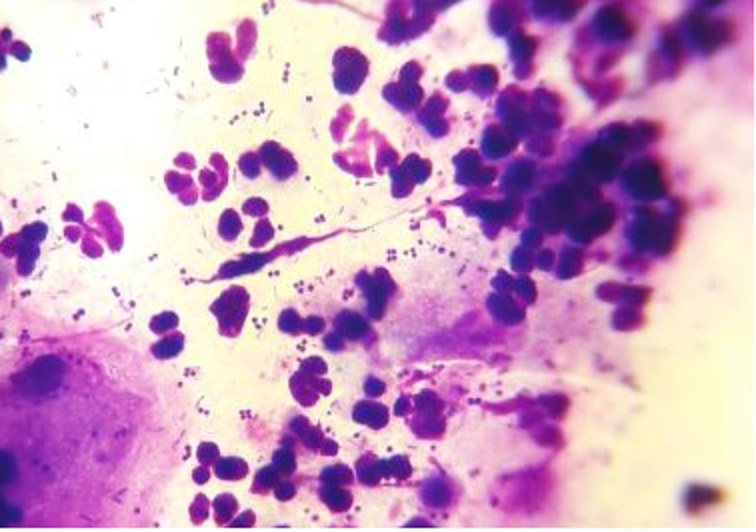

Eine ganz wichtige Untersuchung ist die Zytologie. Man rollt einen Wattetupfer auf einem Objektträger aus und färbt ihn an. Nun kann man erkennen, ob im Ohr ein Pilzproblem oder ein Befall mit Stäbchenbakterien oder Kokken vorliegt. Hat man den Überblick nimmt man einen zweiten Tupfer für die bakterilogische Untersuchung. Da diese Untersuchung ein paar Tage dauert kann man sich nun einer ausgiebigen Reinigung des Gehörganges widmen.